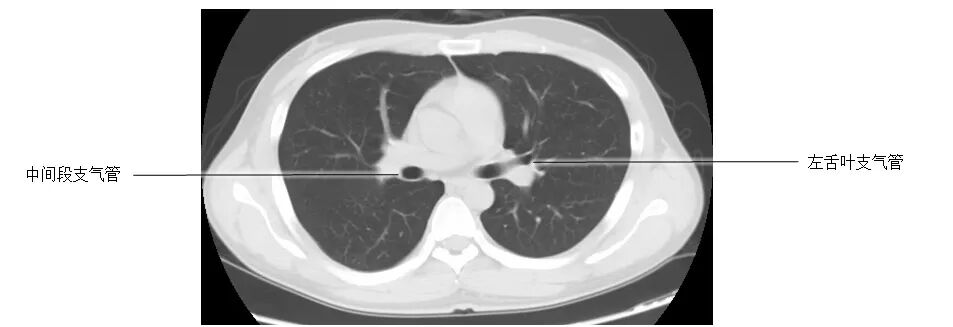

正常胸部CT影像是从横断面显示解剖和病变,可显示的结构包括胸廓、气管和支气管、肺、胸膜、纵隔和膈,CT的重建图像可从各个角度显示胸部解剖情况。不论采用何种图像显示方式,把握基本解剖结构都是必不可少的,一起学习胸部CT肺窗和纵隔窗的正常解剖。

胸部CT肺窗